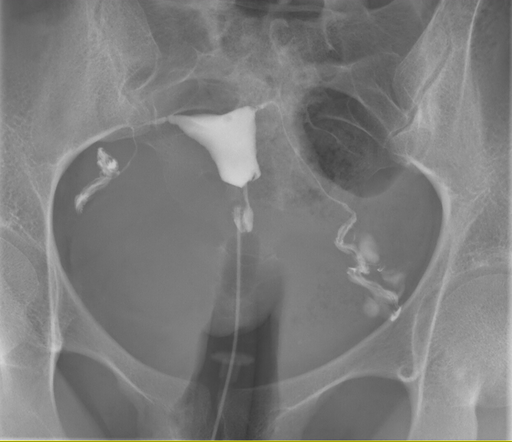

Η Ψηφιακή Υστεροσαλπιγγογραφία (HSG) είναι μια εξειδικευμένη ακτινολογική εξέταση που χρησιμοποιείται για τη λεπτομερή απεικόνιση της μήτρας και των σαλπίγγων. Αποτελεί βασικό διαγνωστικό εργαλείο στη διερεύνηση της γυναικείας υπογονιμότητας, αλλά και στην αξιολόγηση διαφόρων παθολογικών καταστάσεων του γεννητικού συστήματος.

Η Ψηφιακή Υστεροσαλπιγγογραφία πραγματοποιείται σε ειδικά διαμορφωμένο χώρο. Μέσω ενός λεπτού καθετήρα εγχέεται ειδικό σκιαγραφικό υλικό στη μήτρα και λαμβάνονται ψηφιακές ακτινογραφίες σε πραγματικό χρόνο.

Jmarchn, CC BY-SA 3.0 , via Wikimedia Commons